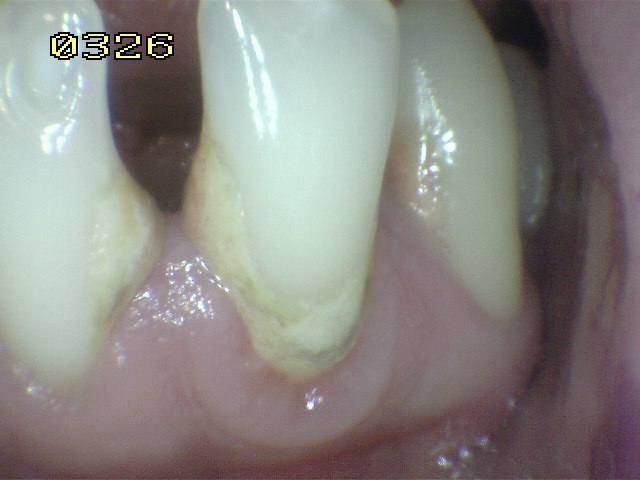

Código E: Si la superficie de la raíz no puede ser visualizada directamente como resultado de la falta de la  recesión gingival, entonces es excluida. Ver imagen inferior izquierda.  Superficies cubiertas completamente por cálculos deben ser removidos antes de determinar el estado de la superficie.

Código 0: La superficie de la raíz no presenta ninguna coloración inusual que lo distingue de los alrededores o las áreas adyacentes de la raíz, ni exhibir un defecto de la superficie, ya sea en la unión cemento-esmalte o totalmente en la superficie de la raíz. La superficie de la raíz tiene un contorno anatómico natural. Ver imagen inferior.

Debe eliminar la placa bacteriana de las superficies (UCE) unión cemento-esmalte por medio del cepillado mecánico o cepillo dental, para poder observar áreas de desmineralización si las hubiere. Ver círculos en amarillo.

Placa bacteriana y saburra

Código 1: Hay una zona claramente delimitada en la superficie de la raíz o en la unión cemento-esmalte (UCE) que es de color (claro, oscuro, marrón y negro), pero no hay cavidad presente, (pérdida del contorno anatómico menor a 0,5 mm) detectable con sonda periodontal.